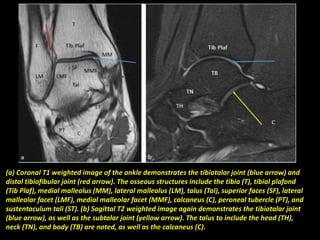

(a) Coronal T1 weighted image of the ankle demonstrates the tibiotalar joint (blue arrow) and

distal tibiofibular joint (red arrow). The osseous structures include the tibia (T), tibial plafond

(Tib Plaf), medial malleolus (MM), lateral malleolus (LM), talus (Tal), superior faces (SF), lateral

malleolar facet (LMF), medial malleolar facet (MMF), calcaneus (C), peroneal tubercle (PT), and

sustentaculum tali (ST). (b) Sagittal T2 weighted image again demonstrates the tibiotalar joint

(blue arrow), as well as the subtalar joint (yellow arrow). The talus to include the head (TH),

neck (TN), and body (TB) are noted, as well as the calcaneus (C).